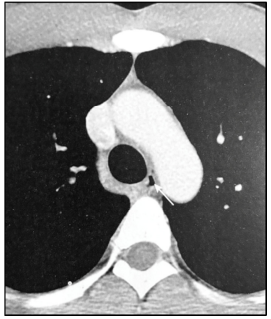

William Herring. Learning radiology: recognizing the basics, 2nd ed., Elsevier, 2012, pg. 101 (com adaptações).

Considerando a imagem digital precedente, formada a partir da aquisição de um exame de tomografia computadorizada (TC), é correto afirmar que essa imagem corresponde a um